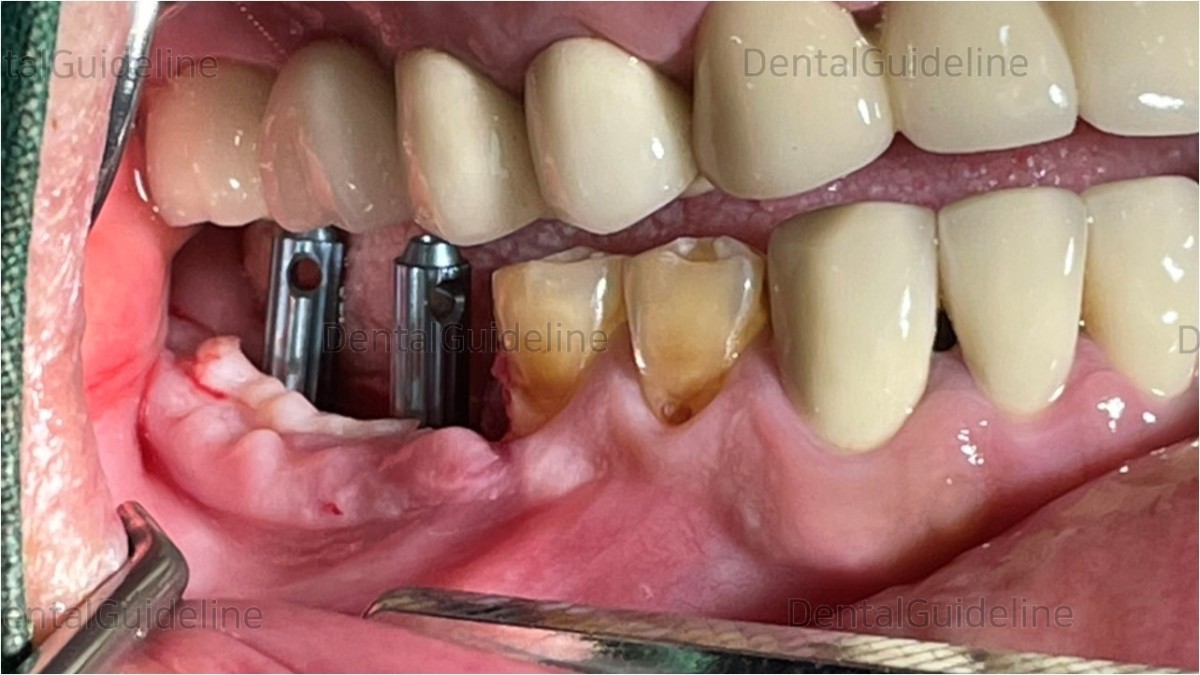

An implant was placed in the 1st molar zone with good initial stability.

positioner

The 2nd implant position was measured using POSITIONER

Re-check the distance between two implants.

ARUM NB1 implant

The implant in the 2nd molar zone also showed good initial stability.

After placing the implant, their position and path were checked with DIRECTION-PIN.